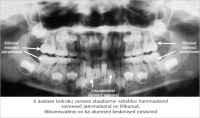

Tööleht Hamba kinnitussidemed

2